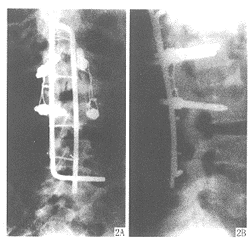

【摘要】 目的 观察经椎弓椎体楔形截骨治疗L1~3 后凸畸形伴不全瘫的疗效。方法 经椎弓椎体楔形截骨,行椎弓根螺钉加短Luque棒或Dick钉内固定。结果 平均随访18个月,后凸角平均纠正42°。Frankel评分进步1~2级,截骨处愈合。结论 该方法治疗L1~3 后凸畸形伴不全瘫 ......